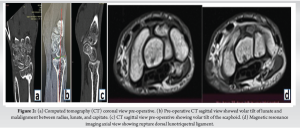

The medical record pertains to a 37-year-old male patient who initially sought medical attention at a different facility subsequent to a fall from a ladder on April 11, 2022. The patient’s instinctive reaction to the fall involved extending his hand to mitigate impact force, resulting in fractures at the distal ends of both radius and ulna [3]. To address these fractures, a closed reduction percutaneous pinning (CRPP) procedure and plaster of Paris (POP) for 6 weeks was performed with the objective of restoring anatomical integrity. Afterward, a physiotherapy program lasting for 6 months was initiated; however, regrettably, there was no observed improvement or advancement in joints’ range of motion (ROM) and grip strength [1]. Importantly, the initial examination following the CRPP procedure did not identify any carpal instability. Following this, evaluations conducted at our facility in January 2023 revealed clinical indications consistent with volar segmental intercalated instability, as seen in X-rays, magnetic resonance imaging and computed tomography scans Figs. 1d and 2a, b, c, d. Furthermore, limitations in ROM were apparent in wrist extension and flexion, as well as wrist supination and pronation as seen clinically presented in Fig. 1a, b, c of the clinical presentation [2,7].